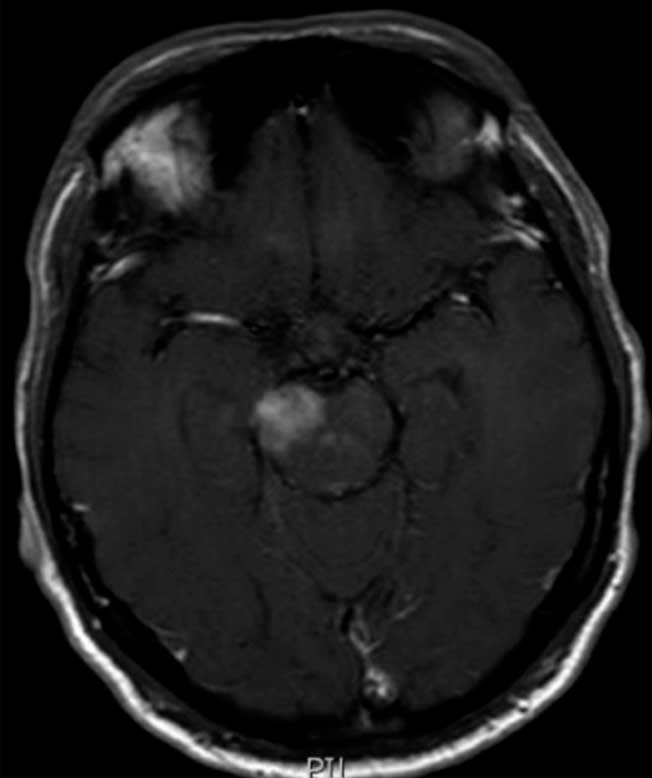

Doença de Neuro-Behçet mimetizando um tumor cerebral

Doença de Behçet é uma síndrome multissistêmica inflamatória de etiologia desconhecida com períodos de relapso e remissões. A condição foi nomeada em memória de Hulusi Behçet, um dermatologista turco o qual descreveu uma tríade de sintomas, caracterizada por úlceras orais recorrentes, úlceras genitais e uveíte. Posteriormente, estudos demonstraram o padrão multissistêmico dessa condição, a qual pode comprometer vasos, articulações, o trato gastrointestinal, o coração, pulmões e o sistema nervoso central (SNC). A doença pode afetar todos os tipos de vasos sanguíneos, tanto a parte arterial quanto a venosa. Poucos casos de DNB mimetizando um tumor cerebral foram reportados. Nós ilustramos um caso de um paciente com um diagnóstico prévio de tumor cerebral- o qual foi diagnosticado como DB. Nós discutimos o caso e revisamos a literatura considerando essa apresentação rara de DB.

Doenca de neuro behcet mimetizando um tumor cerebral